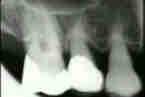

Las radiografías muestrán que ha  perdido cantidades significantes de apoyo del diente y el hueso alveolar se redujo a más de la la mitad de las longitudes de la raíz en muchos de los dientes restantes. También puede notarse en las radiografías que la configuración del hueso alveolar es irregular con la formación de bolsas infraóseas adyacente a los dientes. En los molares la división entre las raíces está desprovista de apoyo de hueso. Este hecho también es obvio al examen clínico (lesión de furcación)